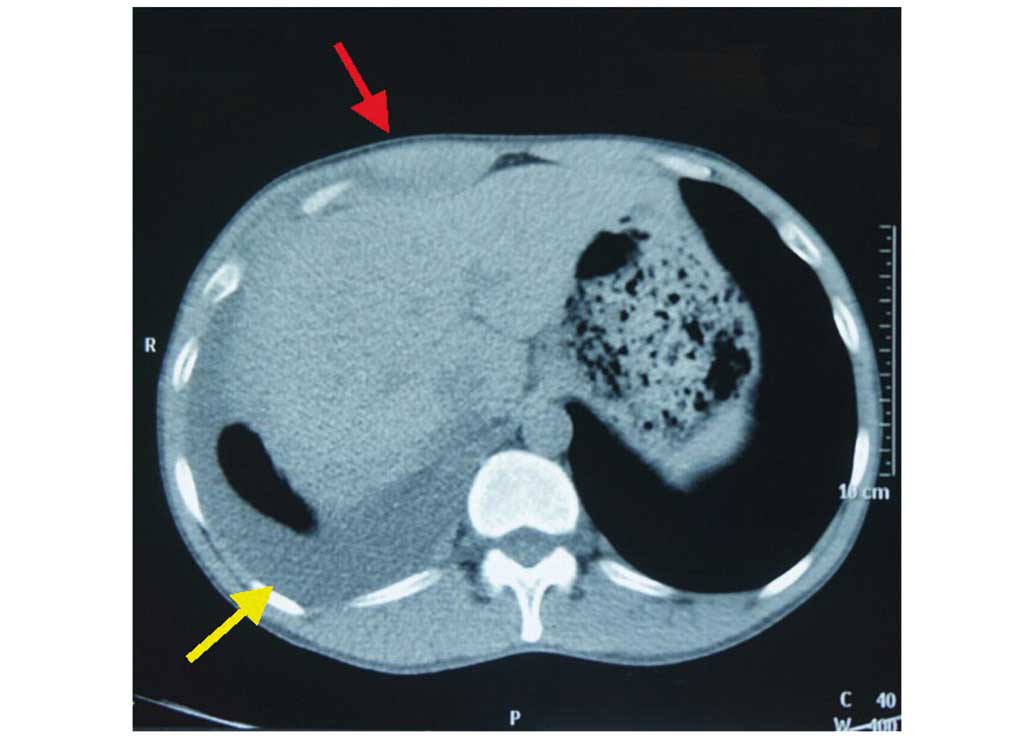

Paragonimiasis mimicking chest cancer and abdominal wall metastaisis: A case report

Typical human paragonimiasis demonstrates an elevated eosinophil count, positive immunoblot, nodular shadows of the lung and pleural thickening with pleural effusion, and these symptoms may be confused with chest cancer. In the present case, a rare case of human paragonimiasis mimicking chest cancer and abdominal wall metastasis is described, the 39‑year‑old male patient was admitted in our hospital for cough, weight loss 5 kg and a firm mass in right upper abdominal wall. The laboratory test showed unremarkable hematology and biochemistry results. Chest X‑ray, Plain computed tomography of the chest and abdomen showed right pleural effusion, several nodules in right lower lung and a mass in the right upper abdominal wall. The initial diagnosis was lung or chest cancer with abdominal wall metastasis, and the abdominal wall mass was resected for the final diagnosis. The biopsy revealed eosinophilic granuloma with Charcot-Leyden crystal formation infiltrated in the muscular fibers. Subsequent to assessment of the antibodies against parasites, the final diagnosis of paragonimiasis was made.